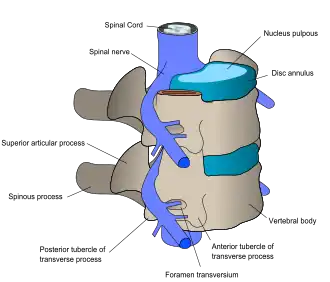

| Spinal nerves exit the spinal cord between each pair of vertebrae. | |

Spinal cord injury can be traumatic or nontraumatic,[5] and can be classified into three types based on cause: mechanical forces, toxic, and ischemic from lack of blood flow.[6] The damage can also be divided into primary and secondary injury: the cell death that occurs immediately in the original injury, and biochemical cascades that are initiated by the original insult and cause further tissue damage.[7] These secondary injury pathways include the ischemic cascade, inflammation, swelling, cell suicide, and neurotransmitter imbalances.[7] They can take place for minutes or weeks following the injury.[8]

At each level of the spinal column, spinal nerves branch off from either side of the spinal cord and exit between a pair of vertebrae, to innervate a specific part of the body. The area of skin innervated by a specific spinal nerve is called a dermatome, and the group of muscles innervated by a single spinal nerve is called a myotome. The part of the spinal cord that was damaged corresponds to the spinal nerves at that level and below. Injuries can be cervical 1–8 (C1–C8), thoracic 1–12 (T1–T12), lumbar 1–5 (L1–L5),[9] or sacral (S1–S5).[10] A person's level of injury is defined as the lowest level of full sensation and function.[11] Paraplegia occurs when the legs are affected by the spinal cord damage (in thoracic, lumbar, or sacral injuries), and tetraplegia occurs when all four limbs are affected (cervical damage).[12]